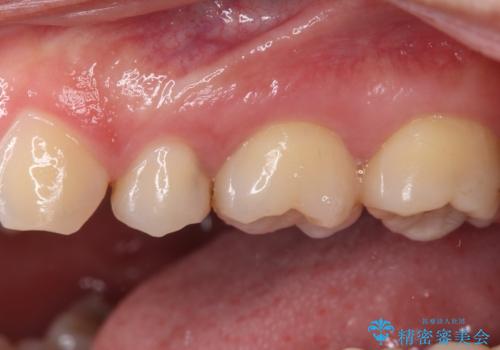

奥歯に物が挟まる セラミックインレーでのむし歯治療

- 食事の度に物が挟まるとのことで来院された患者様です。

目視でも欠損が認められ、レントゲン写真からもむし歯が認められる状態でした。

患者様と相談の上、セラミックインレーで精密な修復治療を行うこととしました。

精密な型取りと、ラバーダム防湿下での接着操作により、歯と詰め物の隙間を最小限にとどめることができ、良好な長期予後が期待できます。